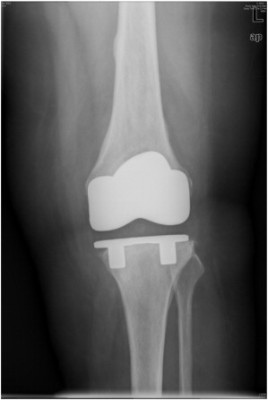

After years of legal maneuvering and court proceedings, the plaintiffs who filed product liability lawsuits against Zimmer Biomet regarding the defendant’s NexGen knee implant have agreed to a settlement arrangement. The news will likely be a huge relief to these plaintiffs, who have been waiting... Read More